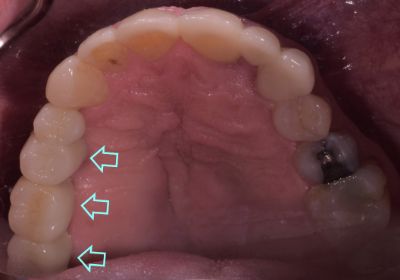

Dental implants are small titanium screws or posts placed in the jawbone where teeth are missing. Over several months, the surrounding jawbone fuses with the implant, forming a solid foundation for artificial teeth. Once the implants are integrated with the jawbone, abutments are attached. These are metal clips that connect the implant to a permanent crown, which replaces the visible part of missing teeth.

Dental implants not only replace any missing teeth with natural-looking replacement teeth, but they also help preserve the bone structure of the face and jawbone and prevent the shifting of any remaining teeth. But for most patients, the most significant advantage of dental implants is not having to worry about or care for dentures or dental bridges.

When the implants have healed and your replacement teeth are completed, we attach the new teeth to the implants using abutments (small metal clips or collars to connect the two pieces permanently). The process takes between six and eight months, from the initial appointment to the final results for most patients. However, the benefits are tremendous. The results can last a lifetime, renewing your self-confidence and restoring your ability to eat whatever you like without worry or embarrassment.

- Looks Natural: We work closely with our patients to create crowns or fixed dentures that match your natural teeth. Color matching, sculpting, and 3D design software work together, so your replacement teeth look like the real thing, and your secret is safe with us.